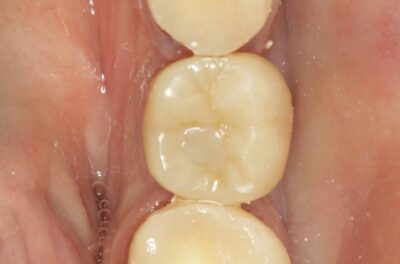

Протезирование коронками из диоксида циркония, после эндодонтического лечения — Исламов Л.А.(01.04.2026)